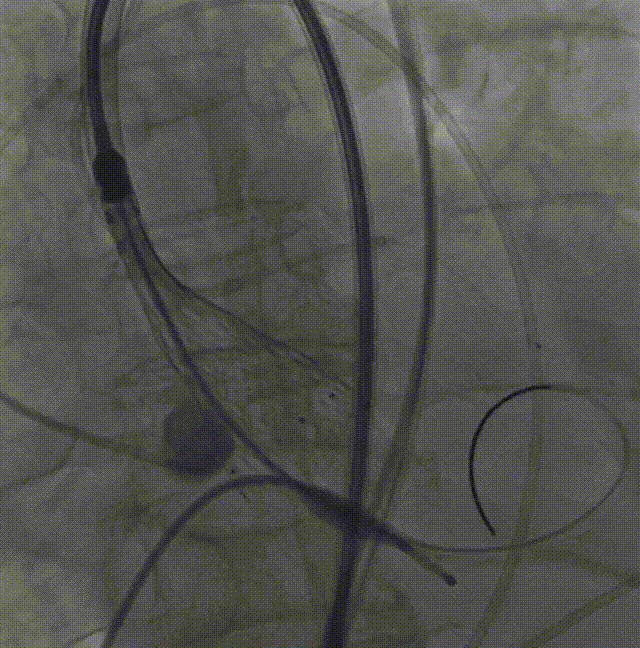

26VenusAplus+snare

瓣膜内22mm球囊后扩张,左冠无显影

LM烟囱支架植入4.0*30mm